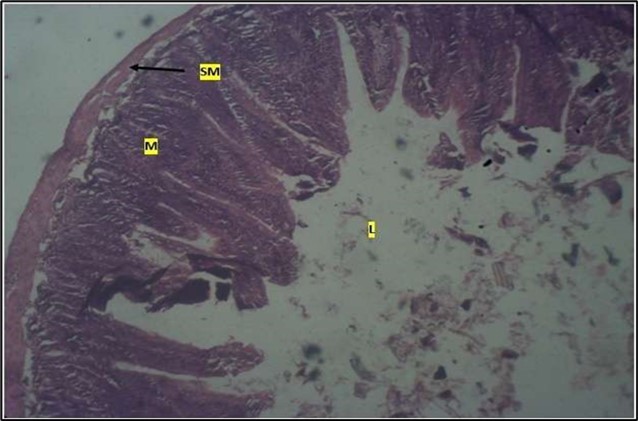

Micrographs of The Small Intestine

Histological examination of the small intestine result in control animals revealed a normal architecture with the red pulp and white pulp with no pathological observation Figure 2. Administration of Abelmoschus esculentus at low dose shows an increased cellularity with numerous cells in the Mucosa and the villi projecting towards the lumen. Focal metaplasia of mucosal cells alongside villous disruption was also observed (Figure 3). The high dose group showed normal cellular architecture with no villous disruption (Figure 4).

Figure 2.Control showing the mucosa with intestinal villi (v) projecting towards the lumen (l) and the underlying smooth muscle layer (sm) all appearing normal